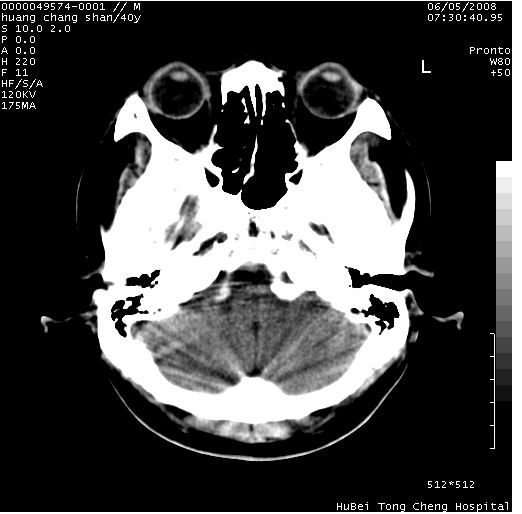

患者 m,40y。头痛,视力模糊,多饮多尿,性欲减退半年余。

行ct平扫+增强,图象如下:

平扫病灶呈等密度,增强后强化明显,均匀一致,结合病史首先考虑:垂体瘤。脑膜瘤不支持,因为脑膜瘤平扫多为实性呈均匀高密度影像,内分泌症状多不明显,垂体内分泌素测定正常。

结合临床考虑鞍上生殖细胞瘤可能性大于脑膜瘤(增强未见脑膜围征),建议结合冠状位扫描看病灶起源及垂体窝、鞍底情况。垂体窝内未见明显软组织密度影,垂体窝未见扩大,暂不考虑垂体瘤;病灶较大,未见囊变及钙化,颅咽管瘤不支持。期待结果!

1、头痛,视力模糊,多饮多尿,性欲减退半年余,提示:肿瘤为功能性肿瘤。

2、ct表现:肿瘤呈类圆形,均匀略高密度,无囊变,无钙化。侧脑室有扩大。

3、首先考虑:功能性垂体大腺瘤。

4、鉴别诊断:脑膜瘤,瘤体内点状钙化最具特征性,常位于鞍结节。颅咽管瘤,蛋壳样钙化,常有囊变。动脉瘤,位于鞍旁,强化与动脉一致。有时尚需与发生于鞍区的生殖细胞瘤鉴别,生殖细胞瘤钙化亦较常见。

5、友情提示:下回发现鞍区占位性病变,最好加扫冠状位,了解肿瘤与蝶鞍的关系及蝶鞍骨质的改变。